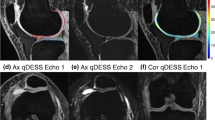

Chondrocalcinosis

Chondrocalcinosis or calcium pyrophosphate crystal deposition (CPPD) has been associated with osteoarthritis; though it is not clear whether it is the result of a systemic process that leads to osteoarthritis, it predisposes to or results from osteoarthritis [32]. The prevalence of CPPD is estimated to be 4–7%, and it is considered a disease of aging [33]. In a recent study assessing a calcium-containing crystal cohort from the Osteoarthritis Initiative, crystal deposition was associated with increased cartilage and meniscal degeneration over a 4-year period. The study suggested that an assessment of the crystal burden may be useful to evaluate risk of onset and worsening of degenerative disease [34]. Imaging methods used for detection of calcifications in articular cartilage and menisci have been x-ray-based, focusing on the conventional radiographs and computed tomography (CT) [32]. In the ACR/EULAR consensus criteria for CPPD diagnosis, MR imaging has not been recommended for the assessment of CPPD, as it has relatively low specificity and historically poor spatial resolution, as compared to other techniques such as CT [35, 36]. The MR imaging literature has described limited use of gradient-echo sequences and DESS (dual echo steady state) with some success, the latter at 3 T and 7 T, for the detection of chondrocalcinosis using CT as a reference standard. In these studies, chondral calcifications appear low in signal intensity on the background of higher signal normal hyaline cartilage. It has been suggested that 7 T MR imaging may offer significantly higher sensitivity in detection of chondral calcific deposits, compared to 3 T MR imaging in patient populations [33]. MR imaging of calcifications in meniscus has been more challenging, even at ultra-high field strength, due to the short T2 nature of both the meniscal tissue and calcifications with similar contrast on standard MR imaging sequences. UTE MR imaging techniques enable direct visualization of meniscal calcification [37]. On UTE MR images, CPPD appears as punctate dark regions within the menisci (Fig. 5). Interestingly, on a study of nine cadaveric knees, calcium pyrophosphate deposits were almost exclusively found in the central avascular zones of the meniscus [32]. Not surprisingly, compared to normal tissue, menisci with crystal deposition had higher indentation stiffness [32].